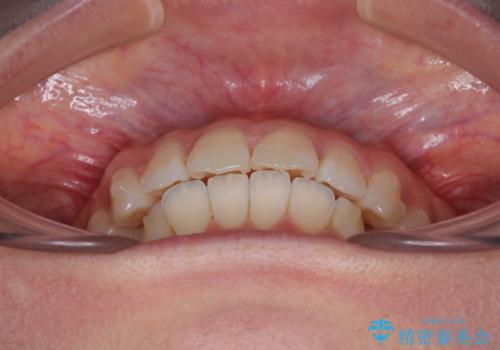

深い咬み合わせによる隙間 インビザライン矯正でコンプレックスを改善

- 上の前歯の隙間を気にして来院された患者様です。

インビザラインにより、上下の歯列を側方に拡大しつつ、前歯の隙間を閉じていくこととしました。

隙間の原因は強い咬合力や舌の突出癖、小帯の異常付着などがありますが、舌のトレーニングをしっかりと行いながら、装着時間を遵守して装着していただいたおかげで、スムーズに治療を終えることができました。